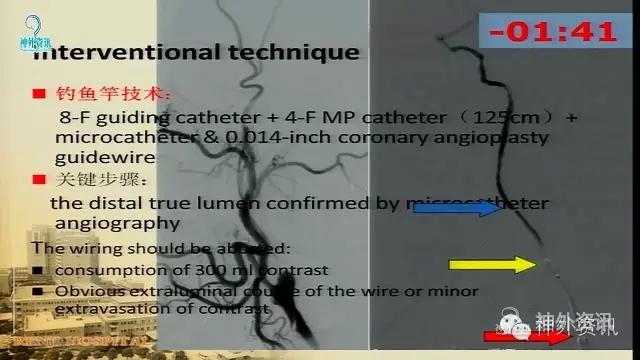

万杰清教授:慢性颈动脉闭塞再通技术及临床效果

擅长脑血管病的治疗研究工作,对动脉瘤性蛛网膜下腔出血的规范化、个体化治疗有独到之处,已成功治愈各种复杂性脑血管3000余例;擅长脑血管病的微创血管内介入和显微外科治疗,包括急性破裂出血的脑动脉瘤、脑血管畸形和硬脑膜动静脉瘘的栓塞治疗,以及颈动脉内膜切除和血管内支架治疗颈动脉狭窄预防脑梗死等。.曾获得仁济医院首届十佳青年,第二医科大学新长征突击手和优秀仁济人—白求恩式的好医生称号,2010仁济医院首届优秀青年临床骨干。分获上海市科技进步二等奖和三等奖。已发表论文30余篇,SCI收录7篇。